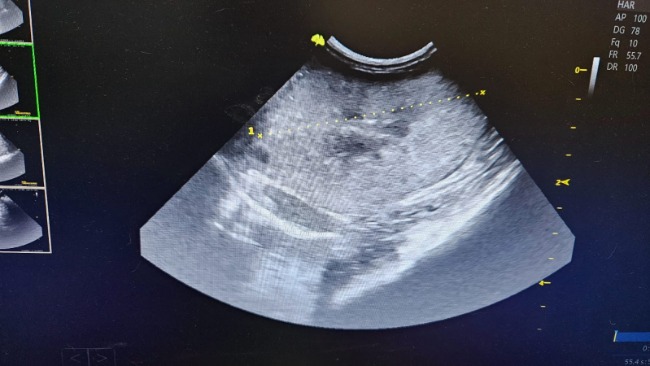

PNN czyli przewlekła niewydolność nerek.

Nieuleczalna. Nerki na usg w złym stanie.

Mocznik,kreatynina parametry bardzo przekroczone. Poza tym jest nieźle.